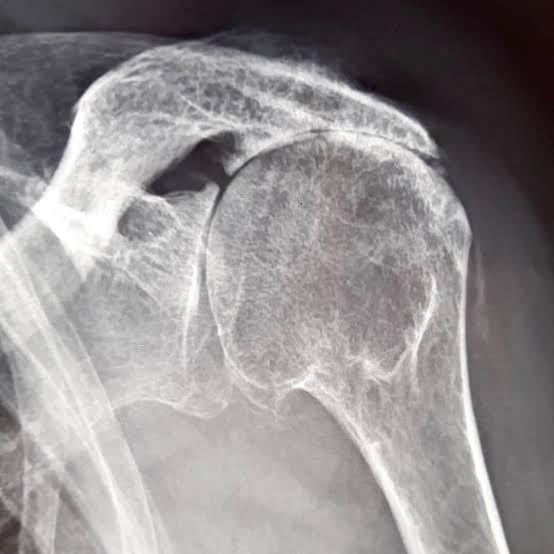

Radiographie d'une arthrose de l'épaule excentrée

Radiographie : Arthrose excentrée de l'épaule

La radiographie standard : face, profil, rotation interne/externe

Elle va apporter une grande partie des informations nécessaires pour évaluer l'arthrose de l'épaule :

• Pincement de l'interligne articulaire (entre la tête humérale et la glène de l'omoplate)

• Condensation de l'os sous-chondral

• Ostéophytes (inférieur, antérieur, postérieur…) - intérêt +++ des clichés en rotation interne/externe

• Forme de la tête humérale (aplatissement, perte de sphéricité…)

• Géodes, lacunes intra-osseuses

• Centrage de la tête humérale (l'excentration avec surélévation serait en faveur d'une lésion associée de la coiffe des rotateurs)

• Évaluation du stock osseux (surtout sur la glène de l'omoplate)